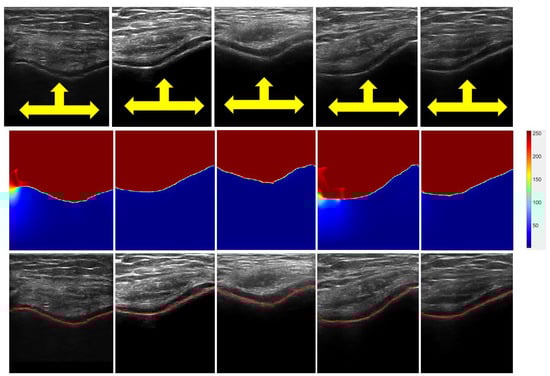

Figure 4.

Bone-surface localization results. Top row: B-mode in vivo US knee scans. Yellow arrows show bone-shadow regions. Middle row: Enhanced bone-shadow image obtained by processing B-mode US scans shown in top row. Soft-tissue interface, red color coding. Bone-shadow regions, blue. Intensity values depict the probability of a signal reaching the transducer imaging array if the signal propagation started at that specific pixel location. The transition region between the soft-tissue and bone-shadow regions represent the expected bone-shadow interface. Bottom row: Localized bone surfaces, shown in red, overlaid on the B-mode US scans.